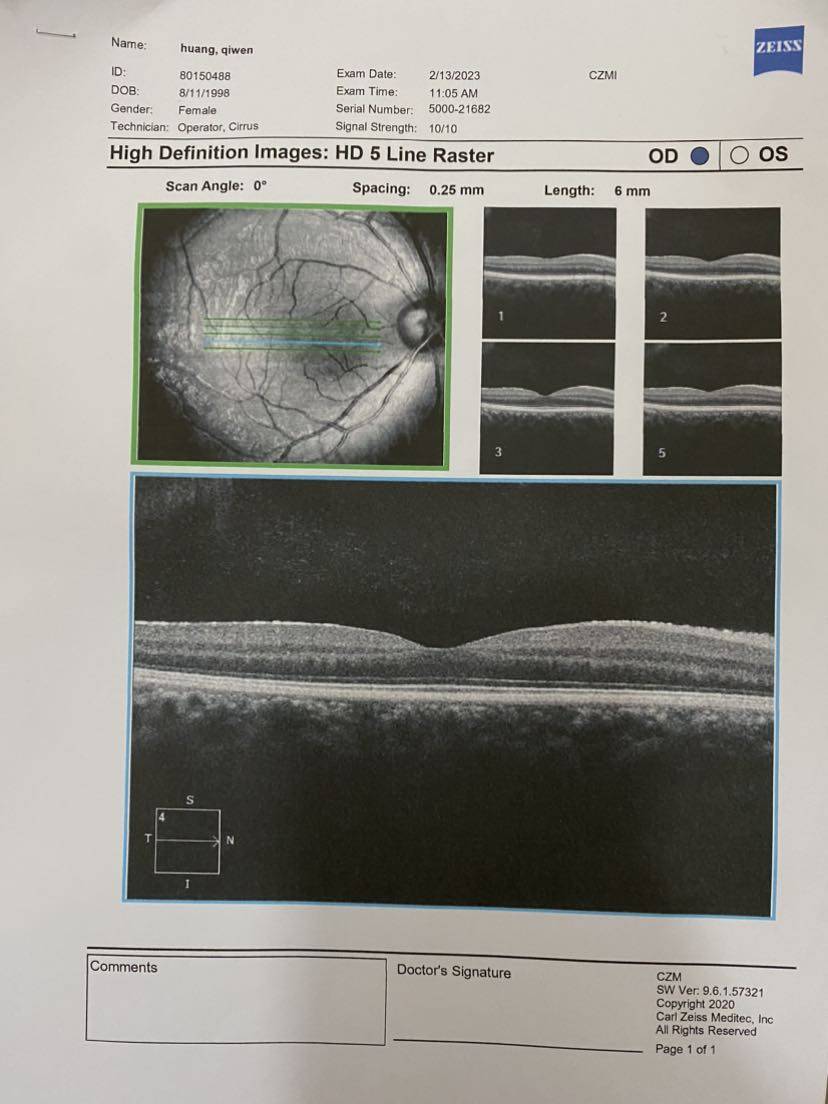

最后把所有报告记录一下,医生说要保管好。千万不能折,那就拍照先留个底吧~

【眼部ct】

哇,这个报告好仔细。

第一次看到这么详细的报告!蛙蛙下次去风湿免疫科复查的时候问问看~

眼部ct多少钱